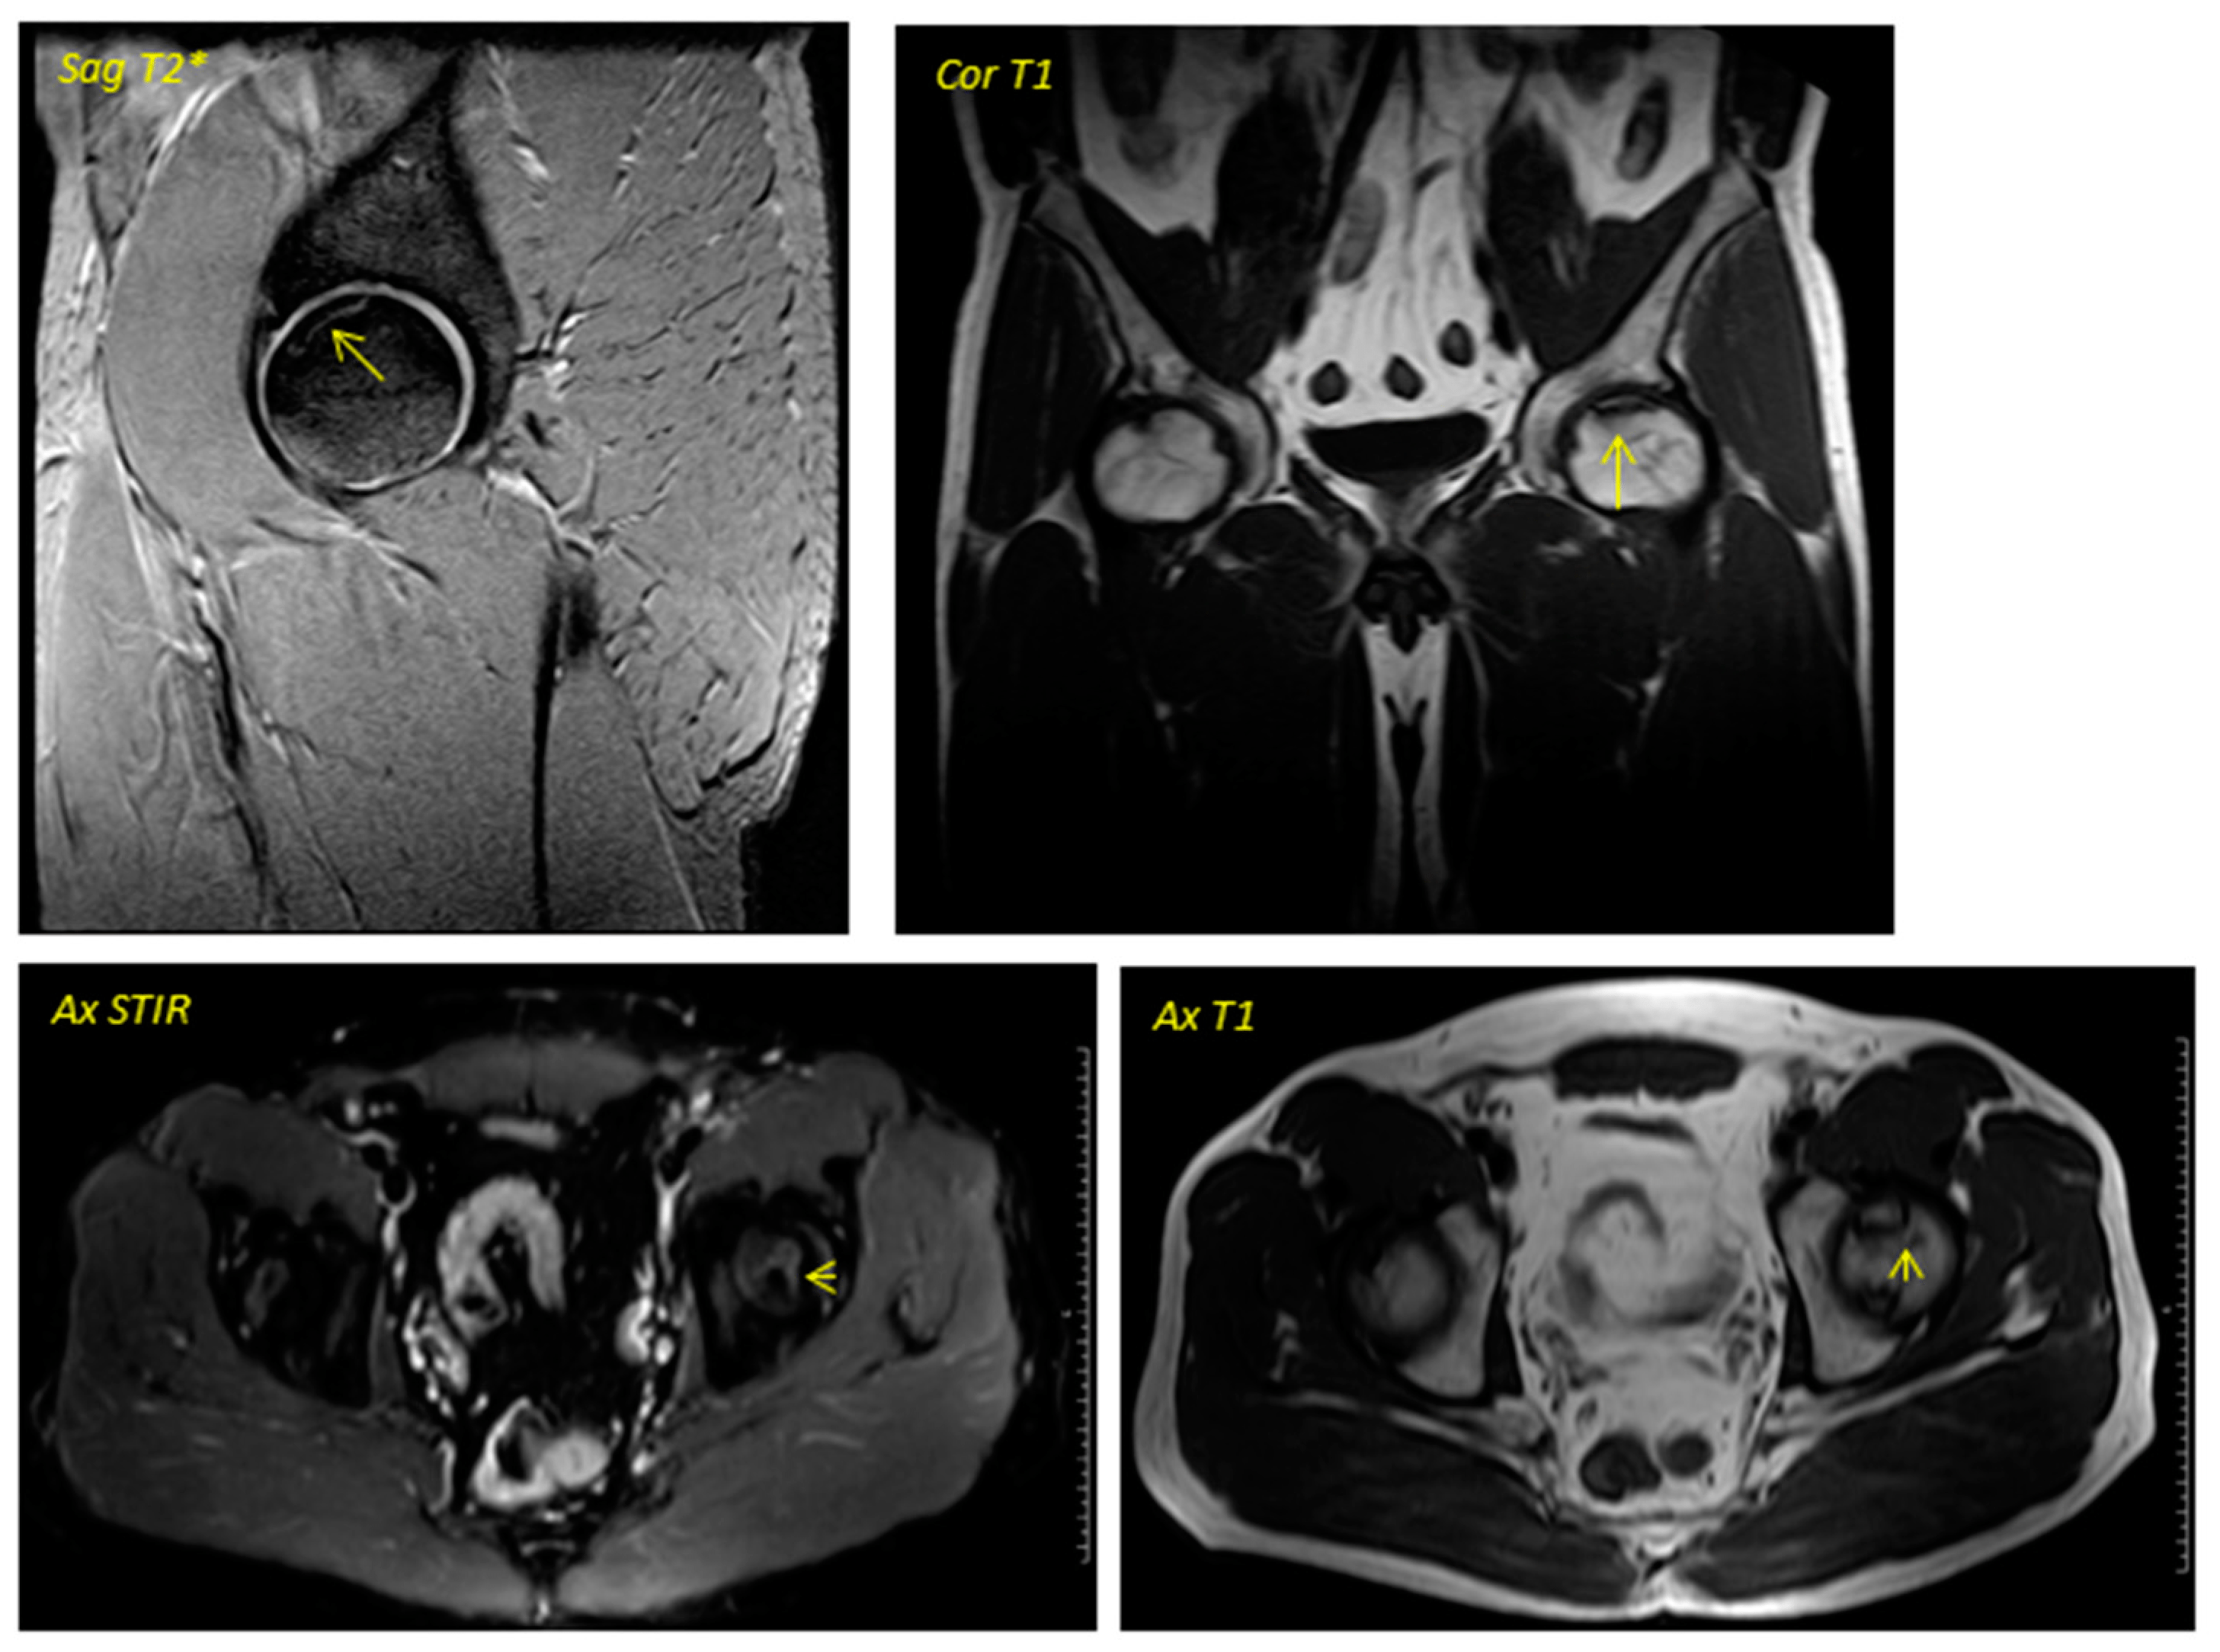

關(guān)于影像學(xué)研究,在12個(gè)月的隨訪(fǎng)期間,在影像學(xué)演變中觀(guān)察到了一些發(fā)現(圖1和圖2)。

首先,方向的變化從第六個(gè)月開(kāi)始出現在所有病例中,而在早期階段并不明顯。其次,62.5%的患者 ( n=5) 在手術(shù)后的第一年內實(shí)現了影像穩定。第三,兩名患者 (25%) 出現壞死區進(jìn)展,而一名 (12.5%) 患者出現明顯的再骨化跡象。盡管觀(guān)察到描述性差異,但后一個(gè)參數的p值在統計學(xué)上并不顯著(zhù)。

圖2:對應于圖1中患者的術(shù)后磁共振成像于2016年4月進(jìn)行